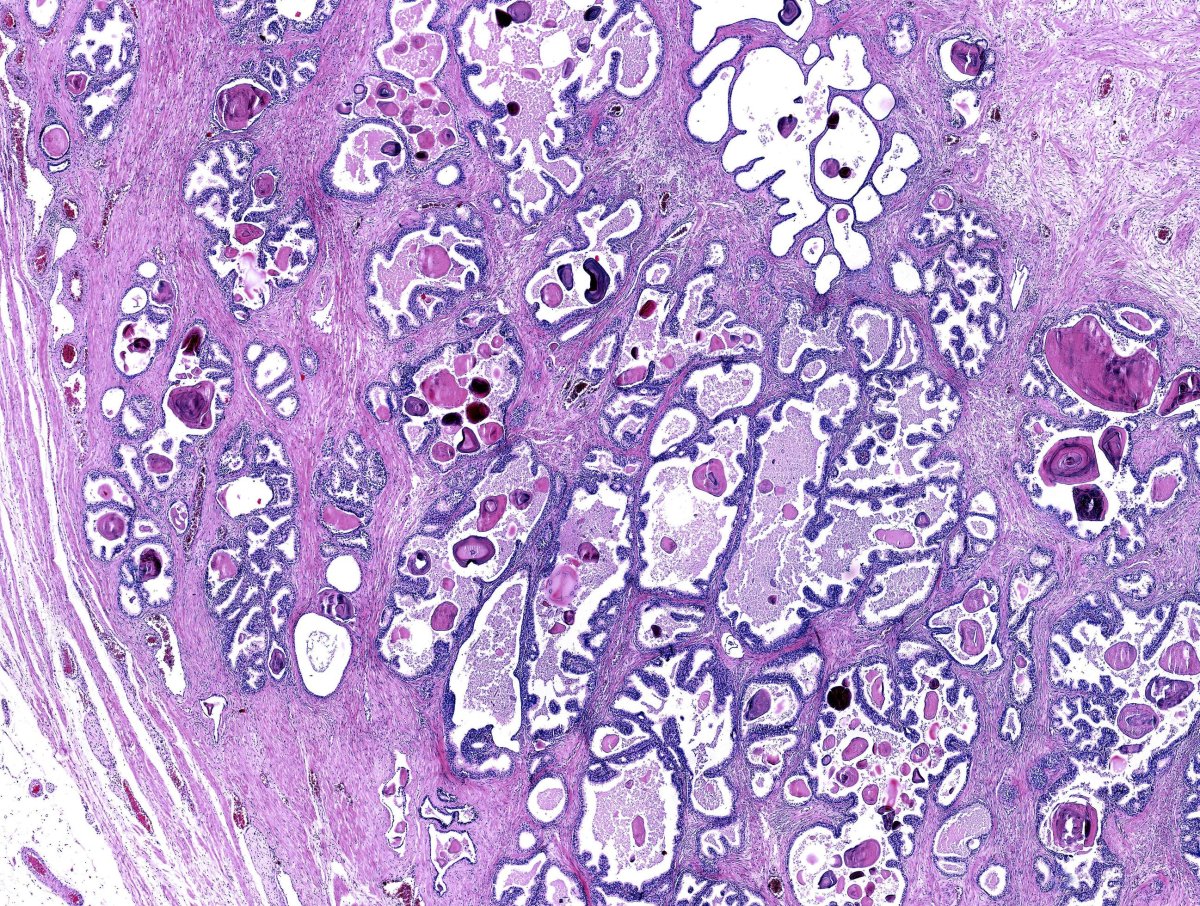

O patologista norte-americano Donald F. Gleason, da Universidade de Minnesota, propôs em 1966 uma classificação arquitetural do câncer de próstata: em vez de avaliar célula por célula, observar como as glândulas tumorais se organizam no microscópio. Quanto mais o padrão se afasta de uma glândula normal, mais agressivo o tumor. Essa ideia simples revolucionou a uropatologia.

A escala original ia de 1 a 5 para cada padrão, e a nota final era a soma dos dois padrões mais frequentes — gerando notas de 2 a 10. Com o tempo, padrões 1 e 2 deixaram de ser usados (correspondem hoje a tecido benigno ou lesões pré-cancerosas), e na prática a escala atual usa apenas padrões de 3 a 5.

Como o patologista atribui o "Gleason"

O patologista observa o material da biópsia ao microscópio e identifica:

• Padrão primário (mais frequente) — recebe um número de 3 a 5

• Padrão secundário (segundo mais frequente) — recebe um número de 3 a 5

• Padrão terciário (eventualmente) — quando há um pequeno foco mais agressivo, geralmente padrão 5

A soma do primário + secundário é o Gleason Score, escrito como "3+4=7", "4+3=7", "4+4=8", etc.

Padrão cribriforme

Glândulas com arquitetura "em peneira", dentro do padrão 4. Quando presente, mesmo em pequena quantidade, é fator de mau prognóstico independente — aumenta risco de recidiva, metástase e mortalidade. Em 2026, deve constar explicitamente no laudo quando identificado, conforme recomendação da ISUP/WHO 2022.

Carcinoma intraductal (IDC-P)

Lesão de altíssima agressividade, frequentemente associada a tumores de alto grau no parênquima adjacente. Sua presença geralmente exclui o paciente da vigilância ativa, mesmo em ISUP 1 ou 2 isolados.

Padrão glomeruloide

Variante incomum do padrão 4 — também associada a comportamento mais agressivo.